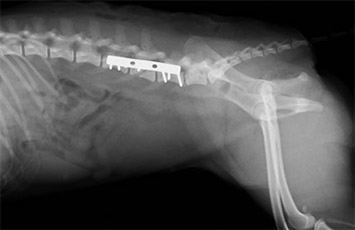

腰椎椎体骨折

-

手術前

手術後

柴犬の飛び出しによる交通事故により発生しました。プレートによる椎体固定を行い、経過良好です。